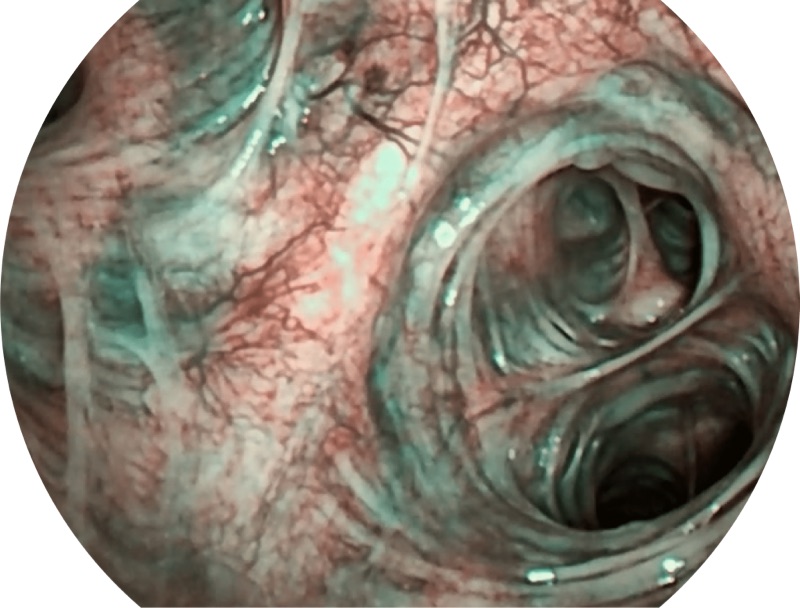

SFI

VIST